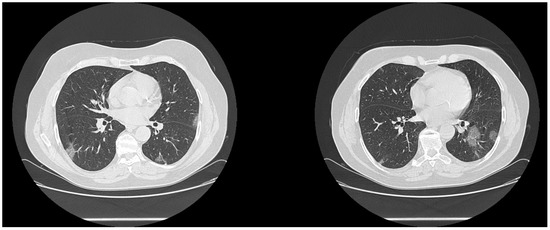

| High diagnostic confidence level | Bilateral multifocal GGO with predominantly peripheral distribution associated or not with septal thickening (crazy paving) and/or consolidations; multifocal GGO of rounded morphology associated or not with crazy paving and/or consolidations; multifocal GGO associated with findings of organizing pneumonia. |

| Intermediate diagnostic confidence level | GGO with diffuse distribution associated or not with crazy paving and/or consolidations; bilateral multifocal GGO and/or consolidations without a prevalent peripheral distribution and without rounded morphology; unilateral GGO with or without consolidation. |

| Low diagnostic confidence level | Isolated small areas of GGO and/or consolidations with non-rounded morphology were included in the low confidence level. |

| Negative for COVID-19 | Cases without the described alterations and with one or more of the following alterations were considered indicative of other diagnoses: isolated lobar or segmental consolidations, presence of solid or caveated nodules, presence of micro-nodules (centro-lobular micro-nodules and “tree in bud” pattern), smooth thickening of the interlobular septa with pleural effusion. |